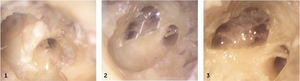

SECUENCIA ANATÓMICA DEL ABORDAJE POR VENTANA REDONDA

1 Ventana redonda (se visualiza los pilares anterior y posterior y la región de la cresta fenestra.

2. Orientación de la espira basal una vez disecada todas las estructuras de la ventana redonda.

3. Situación del final de la espira basal y correlación con la escala vestibular.